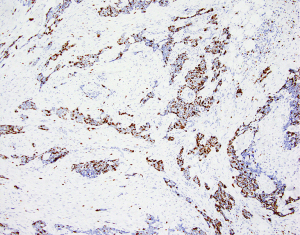

A 72-year-old female patient was referred to the Department of Cranio-Maxillofacial Surgery of the Jagiellonian University in Poland due to the tumor arising from the right parotid gland. The patient was repeatedly operated on in the years 2010 to 2018 in other institution due to recurrence of the BCC of the medial canthal region of the left eyelids. The last recurrence caused infiltration of the left orbit that led to necessity of orbital exenteration in August 2018. Due to inadequate margins of resection, postoperative radiotherapy (PORT) was performed (60 Gy in 30 fractions). After two years of the follow up without recurrence, tumor arising from the parotid gland on the contralateral site was diagnosed. Physical examination revealed that the skin above the tumor was unchanged. The tumor of the parotid gland was not movable. However, we did not observe any signs of peripheral facial nerve paresis. Computed tomography (CT) showed tumor with dimensions 16 mm × 17 mm × 15 mm located in the superficial flap of the parotid gland without penetrating to the deep parotid flap. The tumor adhered to the posterior edge of the masseter muscle and to the lateral surface of the mandibular ramus without bone destruction (Figure 1). There were neither ipsilateral enlarged lymph nodes on the neck nor distant metastases.